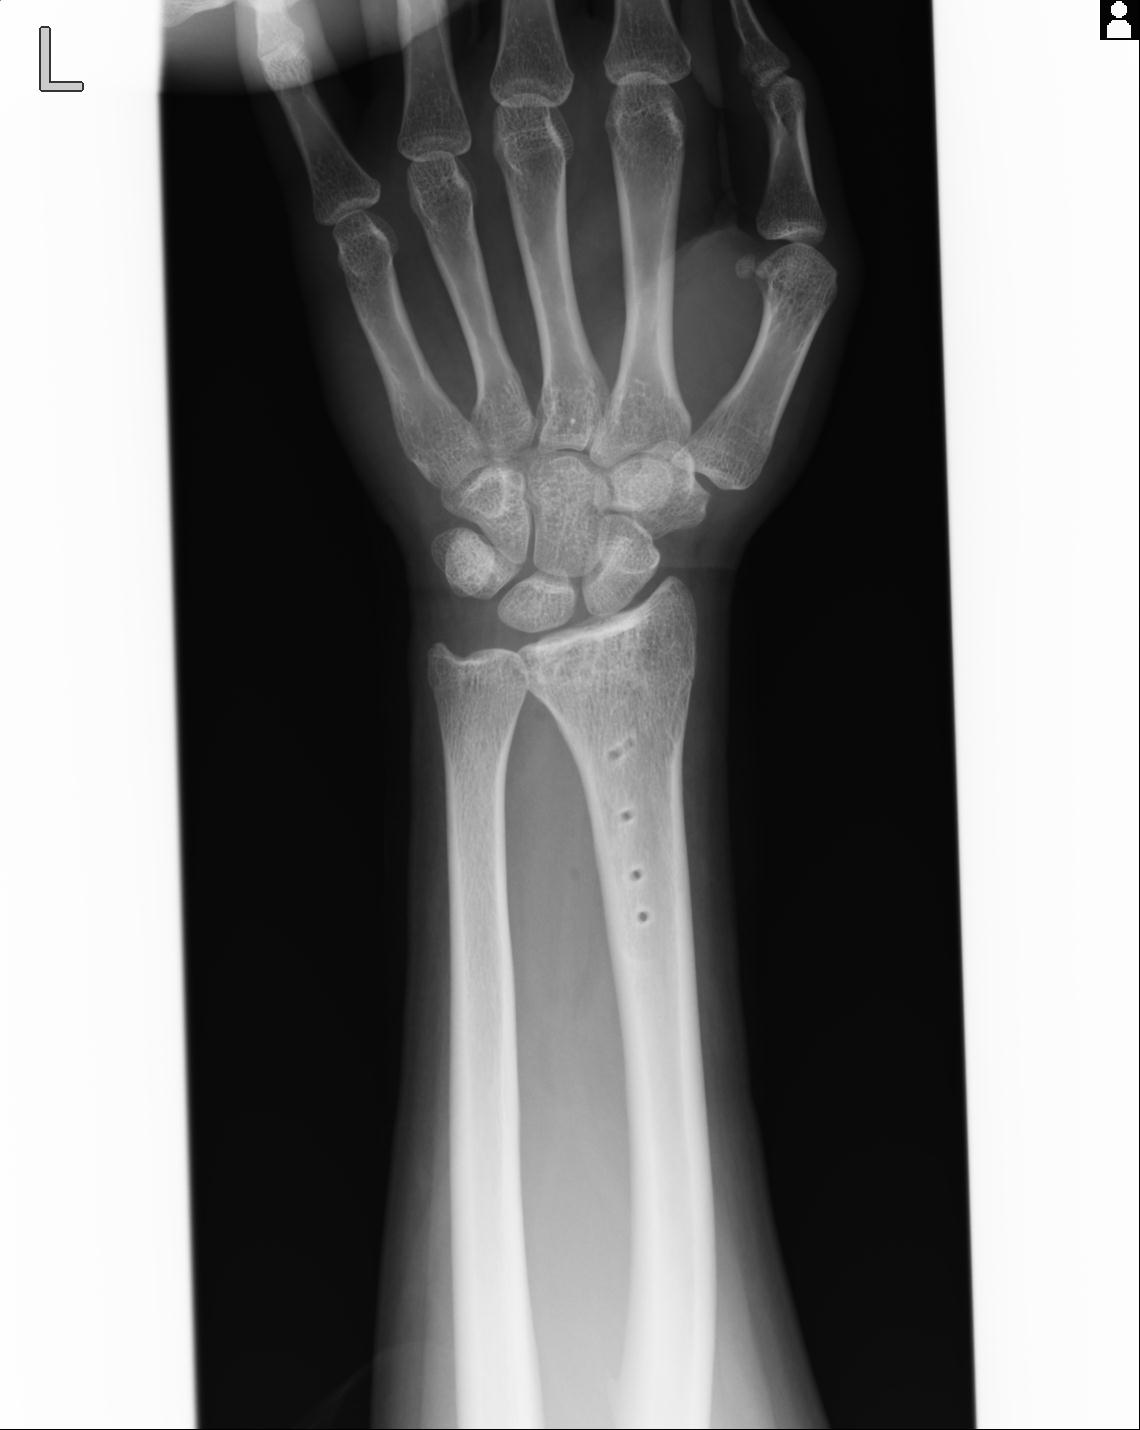

46666 1/23 両股正面+軸と右手関節 2R 76歳女性 右橈骨遠位端

46666 1/28 両股正面+軸と 1/26 右手関節 2R 76歳女性 右転子部骨折